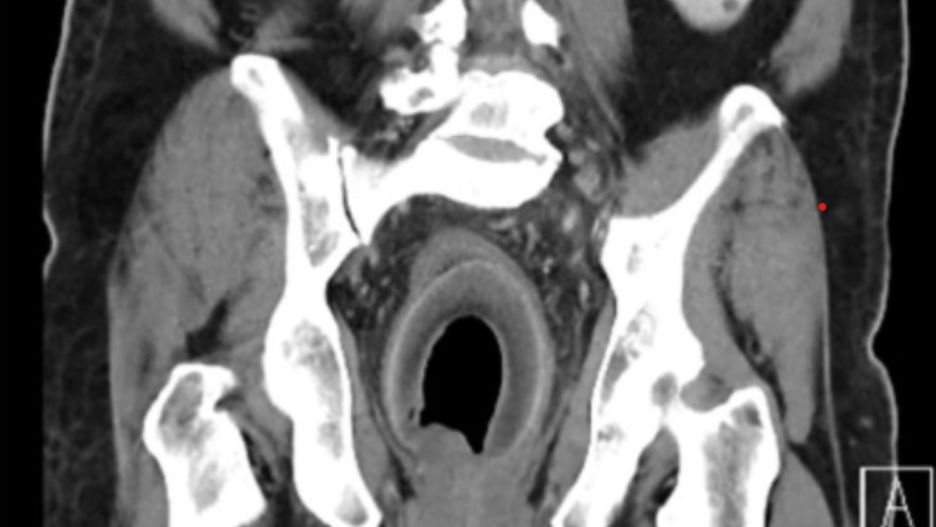

Źródło zdjęć: © British Journal of Surgery

Mężczyzna próbował uporać się z uciążliwymi dolegliwościami za pomocą domowych sposobów. Niestety żadna z metod nie przyniosła ulgi. Kiedy problemy zdrowotne zaczęły się nasilać, zdecydował się zgłosić na ostry dyżur. Tam lekarze wykonali diagnostykę obrazową, która pozwoliła odkryć przyczynę problemów zdrowotnych pacjenta.

Lekarze nie kryli zaskoczenia tym, co ujawniły wyniki badań. Okazało się, że w odbytnicy mężczyzny znajduje się sporych rozmiarów ciało obce. Nie tylko wywoływało zaparcia, ale także uciskało na cewkę moczową, powodując problemy z oddawaniem moczu i dolegliwości bólowe.

Konieczne okazało się przeprowadzenie zabiegu operacyjnego u 59-latka. Chirurdzy wyjęli z ciała operowanego pacjenta kokos mierzący 9 cm długości. "China Times" przekazał, że pęcherz mężczyzny był na skraju pęknięcia. Cofający się mocz spowodowało, że rozszerzył się do około 2000 cm sześciennych.